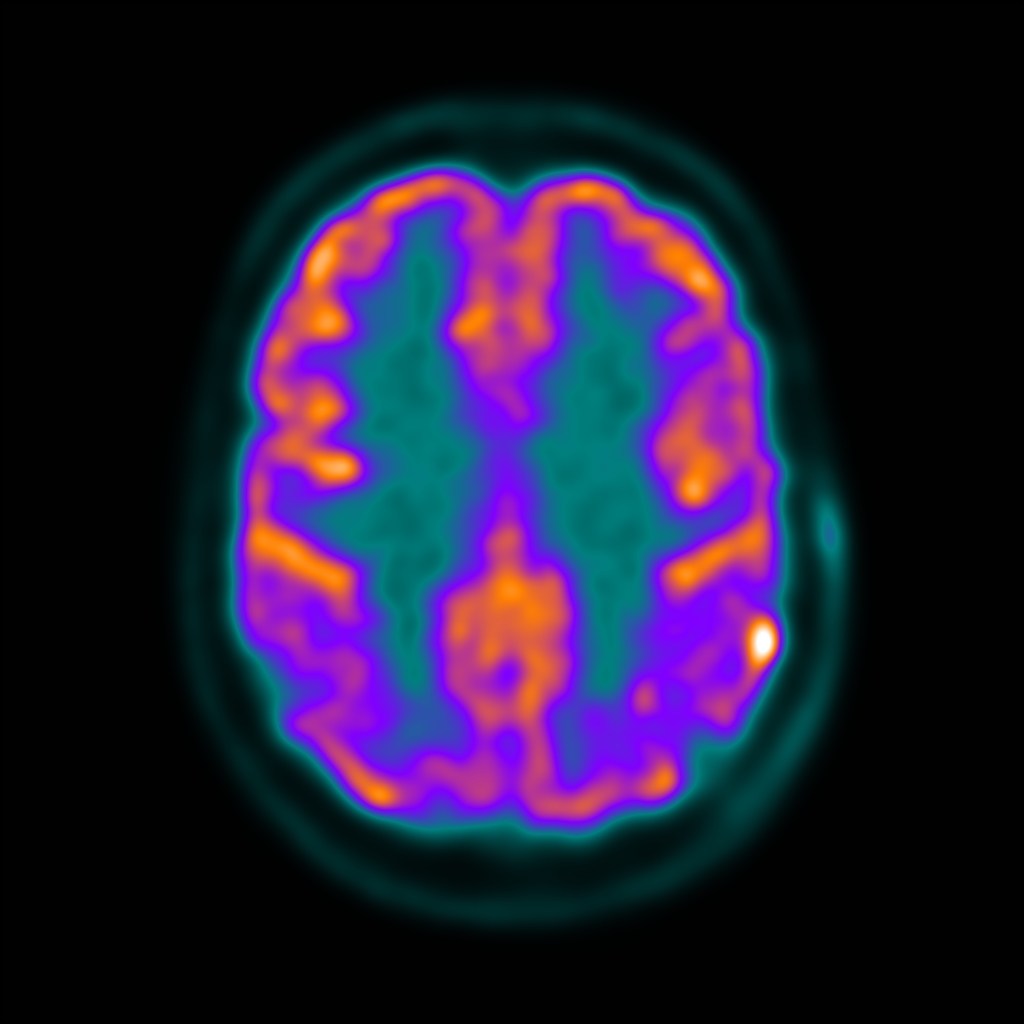

O fludesoxiglicose (18F) é utilizado para fins de diagnóstico através do Tomógrafo por Emissão de Pósitrons (PET), ele é um análogo da glicose ligado ao radioisótopo flúor-18, que se acumula em todas as células que utilizam a glicose como fonte de energia primária.